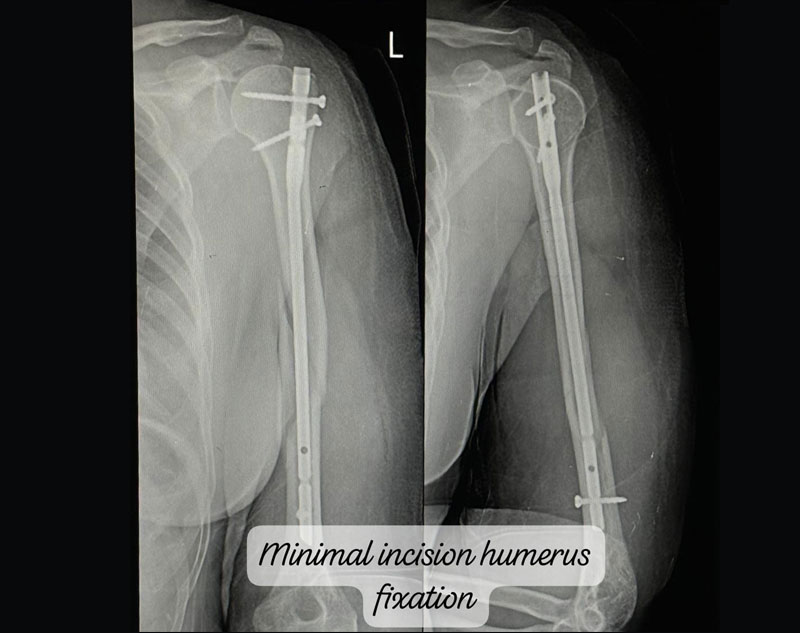

Complex Trauma in orthopedics refers to severe injuries involving multiple or complicated fractures, often combined with soft tissue damage.

These injuries may involve:

Treatment for complex trauma requires a multidisciplinary approach, including surgical intervention, internal/external fixation, and sometimes reconstruction of damaged tissues.